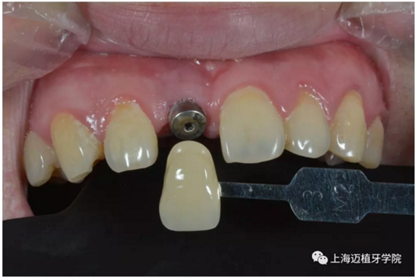

比色:3/M2

氧化鋯個性基臺

戴牙前口內(nèi)照片: